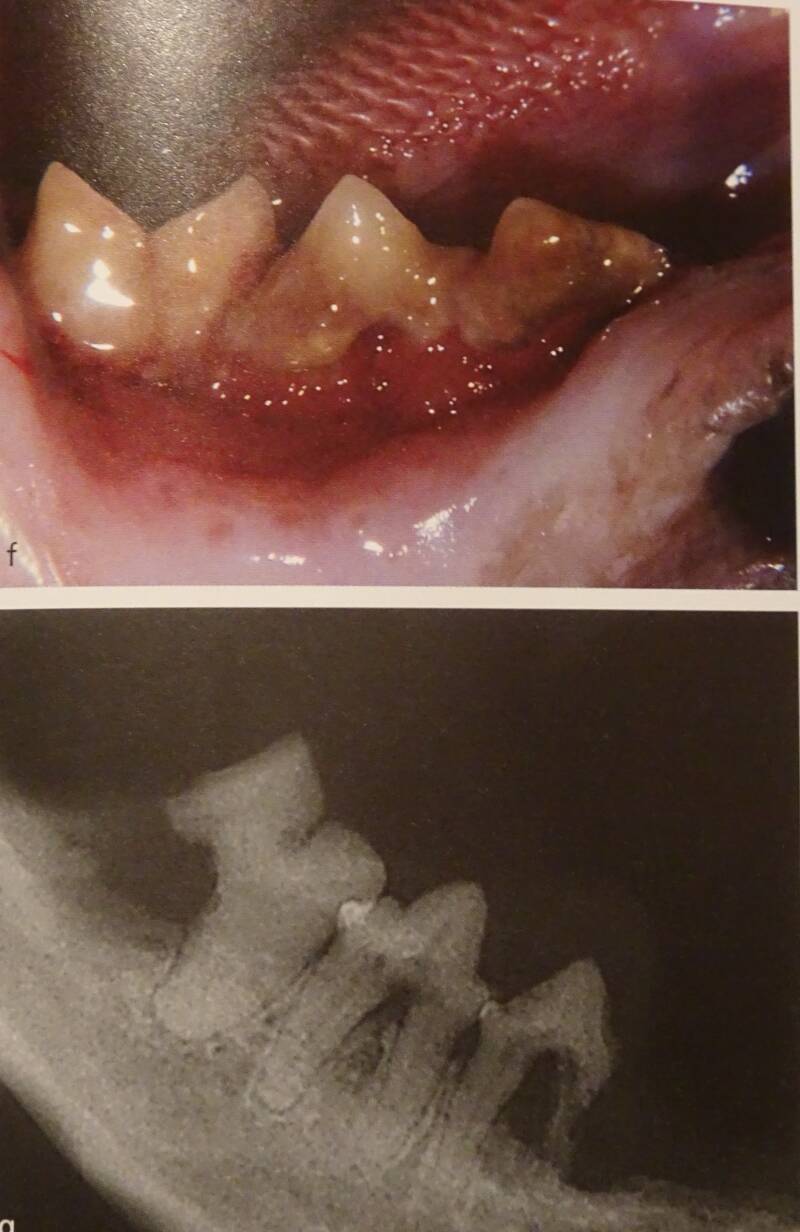

Voorbeelden van verdoken tand problemen . Op radiografie zie je wat zich onder het tandvlees afspeelt.

Voorbeelden van tandbehandeling: Opsporen , blootleggen tandwortel, doorzagen van de tanden en verwijdering van aangetaste tandwortel.